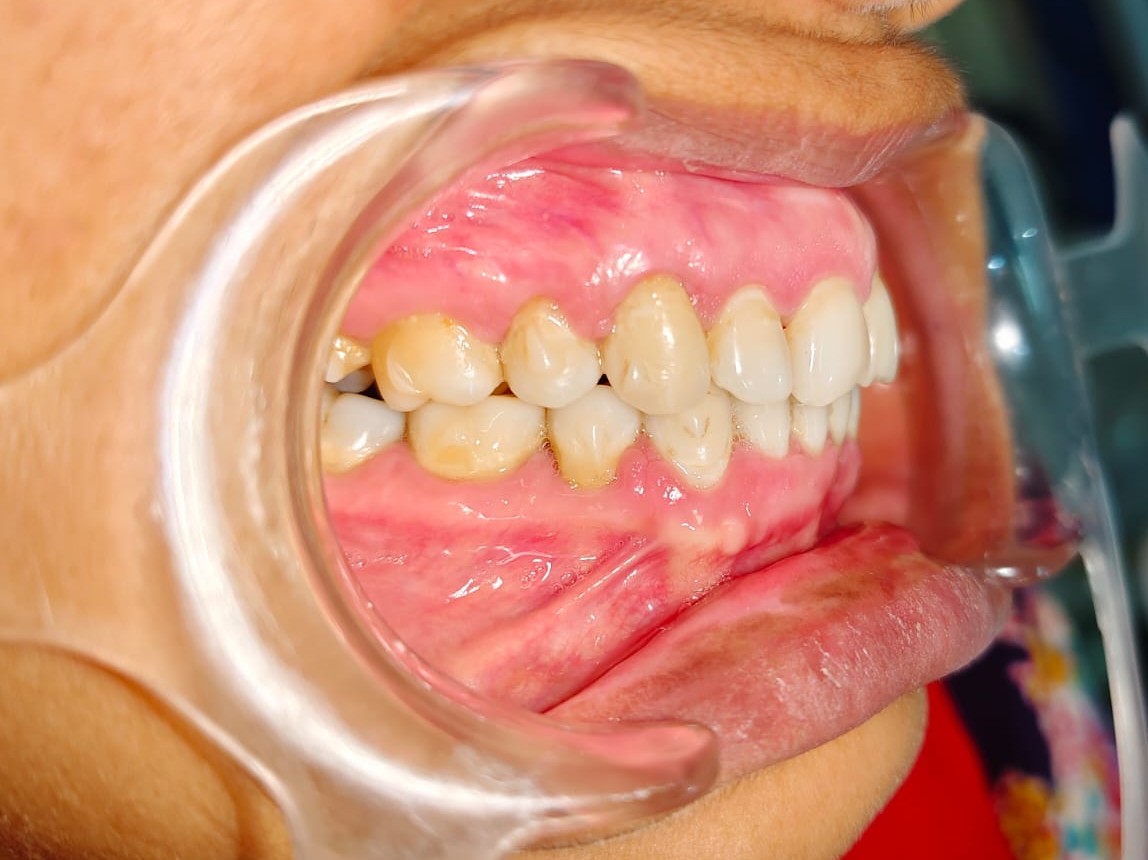

Sairam dental care located in Dharmapuri, with Leading Dentist In Oddapatti, is the Dental Hospital with exclusive root canal, Braces & Invisalign center. Led by renowned Drs Raghuraaman ( Periodontist) and Nivetha Raghuraaman ( Orthodontist) Sairam dental care offers gum treatment with expertise in laser, root canal treatment and digital smile correction with advanced technology aim to focus on aesthetics, comfort and precision. The clinic also specializes in Invisalign treatment, digital smile makeover, laser gum care, dental implants, root canal therapy, extractions and full-mouth rehabilitation blending compassionate care and clinical excellence.